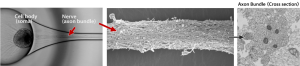

Nerve Organoid™